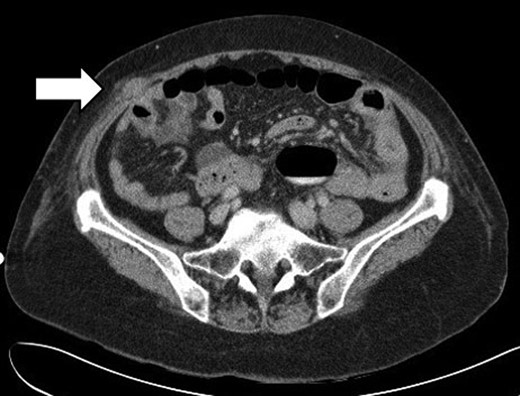

She re-presented on POD 14 with vomiting and abdominal pain. Clinical examination revealed a distended abdomen. A CT scan of the abdomen showed dilated small bowels with a transition point at an ileal herniation through a defect in the right iliac fossa (Fig. 2).

CT scan showing dilated small bowels and a transition point at an ileal herniation through the anterolateral abdominal wall in the right iliac fossa.